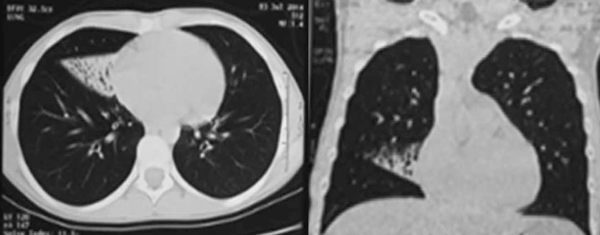

Adolescente de 13 años, sexo femenino, procedente de Montevideo, buen crecimiento y desarrollo, carné esquema de vacunación vigente, medio social, económico y cultural aceptable. Antecedentes familiares de padre y hermana con asma, abuela paterna con asma y aspergilosis broncopulmonar alérgica a los 50 años. La primera evaluación por neumología fue a los 9 años, se presenta con tos crónica catarral desde los 6 meses de vida, sin predominio estacional, no expectoración, drenaje postural, broncorrea, ni sinusitis. Se acompañaba de otitis crónica serosa que requirió colocación de tubos transtimpánicos a los 4 años, con persistencia de secreciones de oído medio, hipoacusia e impedanciometrías alteradas. Al examen se destaca: índice de masa corporal (IMC): 16,7 kg/m² (percentil 15); pleuropulmonar: frecuencia respiratoria 16, saturación de oxígeno ventilando espontáneamente al aire 98%, pico flujo espirado 350 L/m, moviliza secreciones con la tos, no remodelación de tórax, ni hipocratismo digital. No presentaba pólipos en la rinoscopía. Cardiovascular normal. En la radiografía de tórax se observa opacidad inhomogénea en lóbulo medio (Figura 1). La radiografía de senos faciales muestra opacidad de ambos senos maxilares (Figura 2). Con sospecha de bronquiectasias se solicitan estudios para descartar FQ, inmunodeficiencias, malformación congénita de la vía aérea y discinesia ciliar. Los resultados de tres test del sudor fueron normales: Cl 23 meEq/l (159 mg sudor), Cl 14 mEq/l (215 mg), Cl 19 mEq/l (180 mg), y la evaluación inmunológica fue normal. El exudado faríngeo no desarrolló gérmenes. La tomografía de tórax de alta resolución muestra múltiples bronquiectasias en lóbulo medio, disminuido de tamaño por atelectasia (Figura 3). Se realiza fibrobroncoscopía con lavado bronquioalveolar, en vistas de valorar la vía aérea, y valoración infecciosa. Se descarta lesión anatómica o dinámica en la vía aérea y cuerpo extraño, y el estudio bacteriológico y micológico fueron negativos. Con sospecha de DCP, se realiza biopsia de la mucosa bronquial y microscopía electrónica. Las muestras obtenidas fueron fijadas en glutaraldehído al 2,5% en tampón fosfato 0,1 M (pH: 7,2 - 7,4), y trasladadas a 4 grados al laboratorio de biología celular, Instituto de Investigaciones Biológicas Clemente Estable. Se observaron alteraciones ultraestructurales consistentes con DCP. Se realiza cepillado nasal de ambas fosas nasales, observadas vivas e incubadas a 37° al microscopio de contraste de fase en medio de cultivo médium 199 para determinar morfología, frecuencia y patrón de batido ciliar, constatándose movilidad ausente en todos los campos. La microscopía electrónica muestra ultraestructura ciliar con patrón 9+2, con ausencia de ambos brazos de dineína. El diagnóstico de funcionalidad con inmovilidad ciliar absoluta, cilios de ultraestructura con defecto de brazos internos y externos de dineína, confirma la DCP. Se solicita estudio genético molecular con secuenciación del gen DNAH5, que muestra una variante probablemente patológica con presencia en homocigosis de una duplicación c.10196dupT mutación frameshift p. Cys3400Metfsx54, no se encuentra en base de datos ni en la bibliografía consultada, y otra de significado incierto con presencia en heterocigosis de la variante c.A8387G: p.D2796G en el gen DNAH5. En la evolución, la paciente persiste con igual sintomatología, los cultivos de expectoración iniciales fueron negativos. A los 13 años el estudio bacteriológico de expectoración desarrolla Pseudomonas aeruginosa, se realiza tratamiento con gentamicina nebulizada y ciprofloxacina vía oral por 21 días. Los cultivos de control muestran desarrollo de Pseudomonas aeruginosa, por lo que se indica tobramicina inhalada por 28 días. Persiste desarrollo de abundantes colonias y se inicia colistina nebulizada cada 12 horas, inicialmente por tres meses, luego mensual alternando con tobramicina inhalada. De la evolución funcional, presentó espirometrías normales, con valores de volumen espiratorio forzado en el primer segundo (VEF1) estables de 95% del predicho, distancia recorrida en 6 minutos sin desaturación en la mar cha, ecocardiograma Doppler normal y audio metrías normales. En la tomografía de tórax, a los 13 años, persisten bronquiectasias asociadas a atelectasia en lóbulo medio, sin cambios significativos con respecto a la tomografía previa, hiperinsuflación compensadora del resto de los lóbulos; aisladas bronquiectasias en segmento basal medial de lóbulo inferior derecho, aso ciado a imágenes de árbol en brote. Agrega bronco rrea mucopurulenta 10 cc al día. Presentó adecuada adhe rencia al tratamiento con fisioterapia dos veces por día en domicilio, asistida por fisioterapeuta tres veces a la semana. El tratamiento antibiótico continuó con colistina nebulizada y cipro floxacina vía oral. Realiza ejer cicio y danza de forma regular.